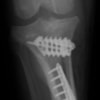

術後写真

手術前後のTPA(脛骨高平部の角度)を測定しています。

約29°から約10°へ矯正されています。

本症例は、走った後に左後肢を挙上していることを主訴に来院されました。触診時に左膝関節のクリック音を聴取、レントゲン検査にて左脛骨の前方変位が認められました。術中に、前十字靱帯の断裂及び内側半月板の損傷、内側の軟部組織の顕著な腫脹を確認。半月板切除、TPLOを実施しました。周囲組織への炎症の波及もあったため回復に時間を要しておりますが、徐々に跛行頻度は減少傾向にあり、現在も経過観察中です。術前に約29°あったTPAは術後に約10°まで矯正されました。